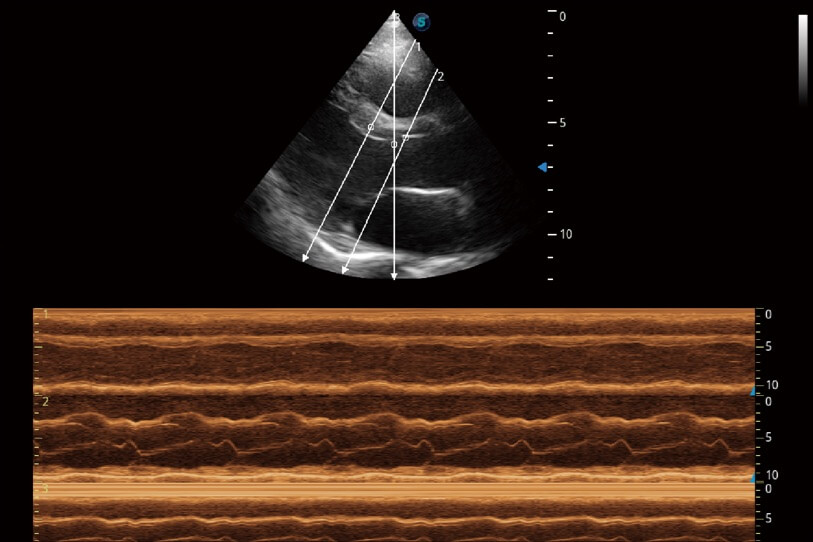

通过360度任意调节3条M型取样线,在同一心动周期上观察心脏不同位置的运动曲线,得到准确的心功能测量数据,有效评估心肌运动及左心室功能。